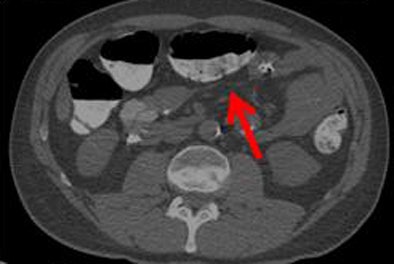

| Poor quality (1, above) means there is significant stool that is incompletely tagged; average (2, below) denotes that some incompletely tagged stool is present; and medium (3, bottom image) represents good overall quality with some stool that is not completely tagged. Superior quality (4) is generally not obtained in reduced-prep regimens. |